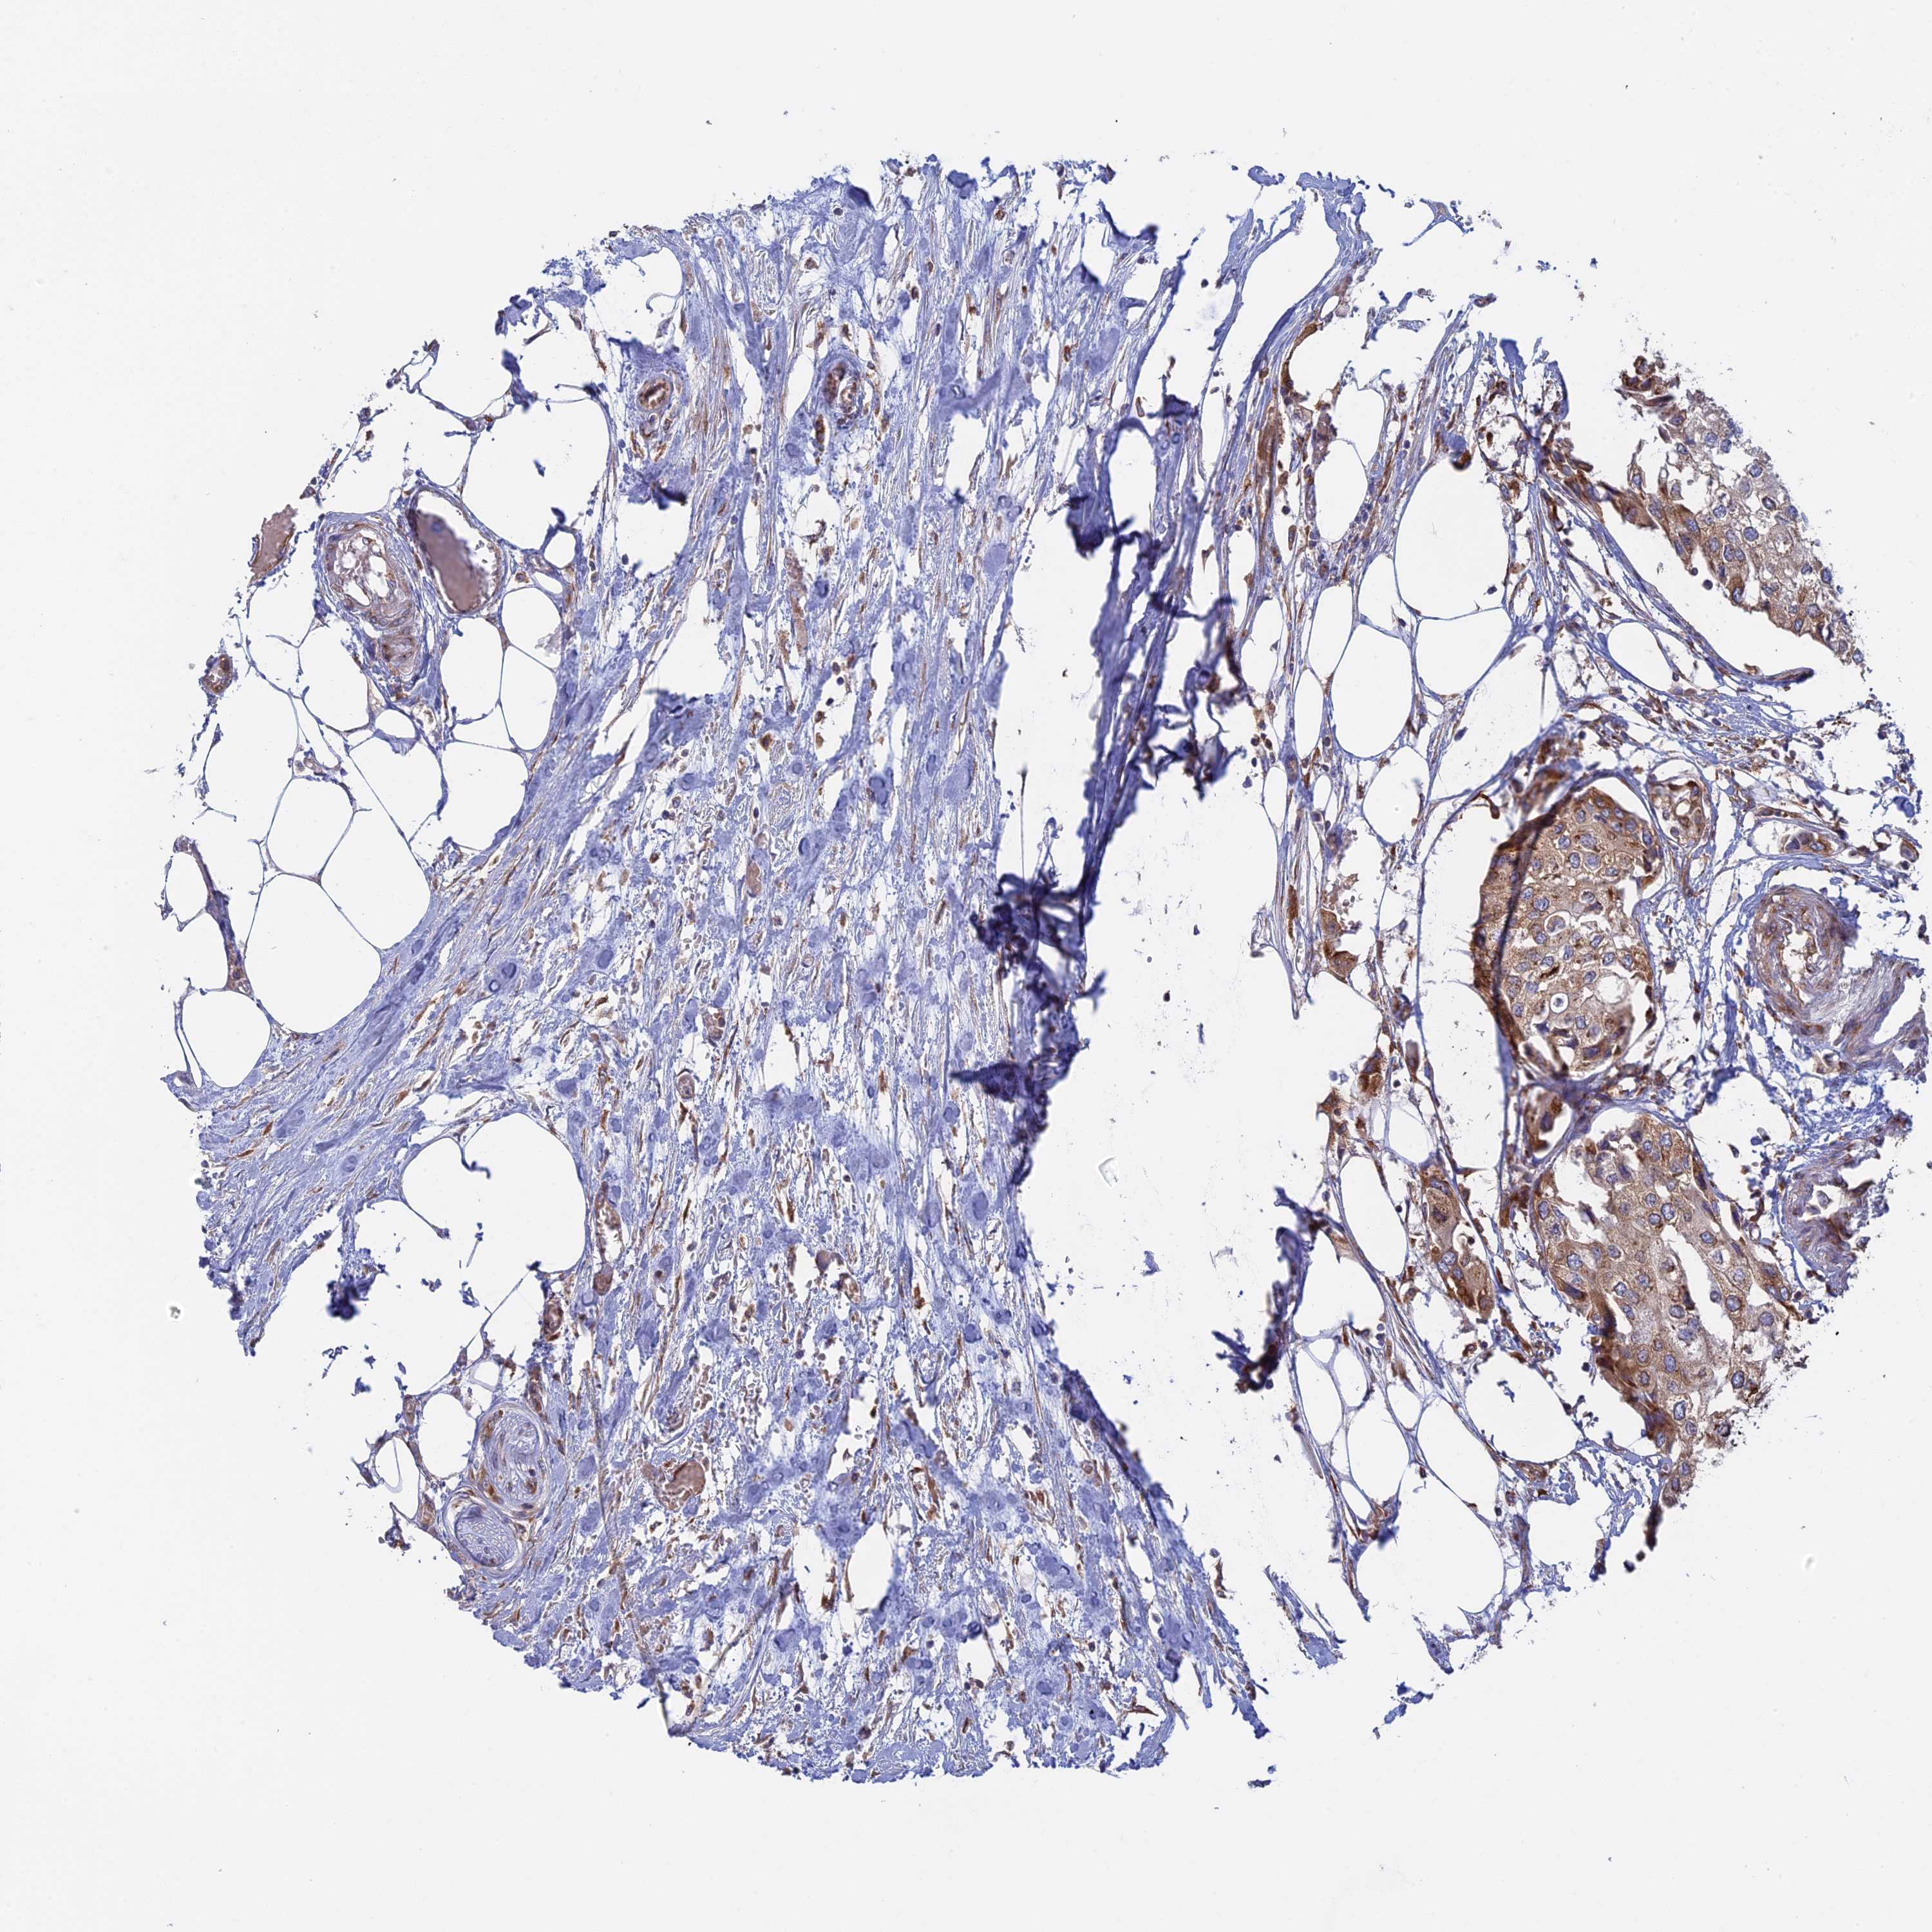

UROTHELIAL CANCER - Protein expressioni

A mouse-over function shows sample information and annotation data. Click on an image to view it in a full screen mode. Samples can be filtered based on level of antibody staining by selecting one or several of the following categories: high, medium, low and not detected. The assay and annotation is described here.

Note that samples used for immunohistochemistry by the Human Protein Atlas do not correspond to samples in the TCGA dataset.

Antibody stainingi

Antibody staining in the annotated cell types in the current human tissue is reported as not detected, low, medium, or high, based on conventional immunohistochemistry profiling in selected tissues. This score is based on the combination of the staining intensity and fraction of stained cells.

Each image is clickable and will lead to virtual microscopy that enables deeper exploration of all samples and also displays staining intensity scores, fraction scores and subcellular localization as well as patient and tissue information for each sample.

Antibody HPA042484

Antibody HPA045481

Staining

High

Medium

Low

Not detected

Intensity

Strong

Moderate

Weak

Negative

Quantity

>75%

75%-25%

<25%

None

Location

Nuclear

Cytoplasmic/membranous

Cytoplasmic/membranous,nuclear

Urothelial carcinoma, High grade

Urothelial carcinoma, Low grade

Urothelial carcinoma, NOS